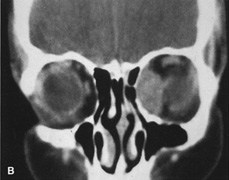

Lateral orbitotomy provides excellent access to deep lesions in the subperiosteal, peripheral, or intraconal space lateral to the optic nerve (Fig. 8A, B).

Fig. 8. Coronal (A) and axial (B) views in an illustration of areas (shaded) amenable to lateral orbitotomy.

Although intraconal lesions medial to the nerve sometimes can be approached laterally, great care to identify and protect the optic nerve is required during deep orbital dissection. Because the eyelid crease incision allows such wide exposure of the superolateral orbit, it is often possible to remove fairly large orbital lesions without removing the lateral orbital wall (Fig. 9). Surgery in this case proceeds as described to exposure of the superior and lateral bony orbital rims. It is not necessary to reflect periosteum over the external surface of the rim. Instead, once periosteum at the rim is exposed, it is cut with cautery and then only the mesial periorbita need be elevated internally to expose orbital contents with subsequent intra-orbital dissection carried out with the lateral rim in place. Often it is preferable to initially attempt to remove intraconal or lacrimal fossa lesions in this fashion. If exposure proves inadequate, the periosteum over the external surface of the lateral orbital rim can be elevated and osteotomies and removal of the lateral wall still can be carried out.

Fig. 9. A,B. Coronal and axial CT images of a large intraconal neoplasm. C. Because it was felt to represent a well-encapsulated cavernous hemangioma, this lesion was a candidate for removal via an eyelid crease orbitotomy without bone removal. The eyelid crease incision marked. D. Incision made with scalpel. E. Orbicularis muscle is tented up and incised to expose the underlying septum. F. Dissection of a skin-muscle flap deep to orbicularis exposes the orbital septum and superior orbital bony rim. G. Cutting cautery is used to incise periosteum along the superior and lateral rims; finger palpation of the bone helps to direct this incision. H. Periorbita is elevated along the mesial surface of the lateral orbital rim in order to expose the deep orbital tissues. I. The cavernous hemangioma is visualized in the wound. Retraction is provided by one or more malleable retractors. J. Cryoprobe is affixed to the hemangioma to facilitate manipulation of the lesion. K. Large cavernous hemangioma after removal through the eyelid crease incision which was accomplished without bone removal. L. Periorbita is reattached over the lateral rim. M. The eyelid crease incision is closed with a running suture.